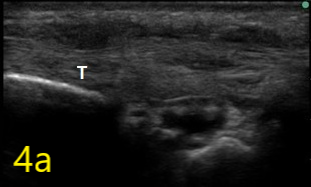

Image 4a

Ultrasound in Orthopedic Practice